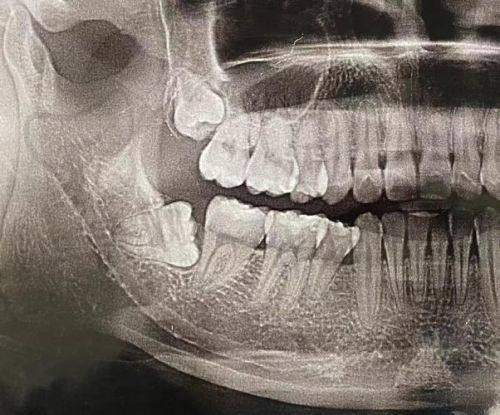

在设备上,配备了精良的齿科设备。数字化拍片设备可以清晰地显示乳牙的位置、牙根情况等,帮助医生更正确地制定拔牙方案。这些精良的设备为乳牙拔除提供了有力的技术支持,提高了拔牙的安心性和成功几率。